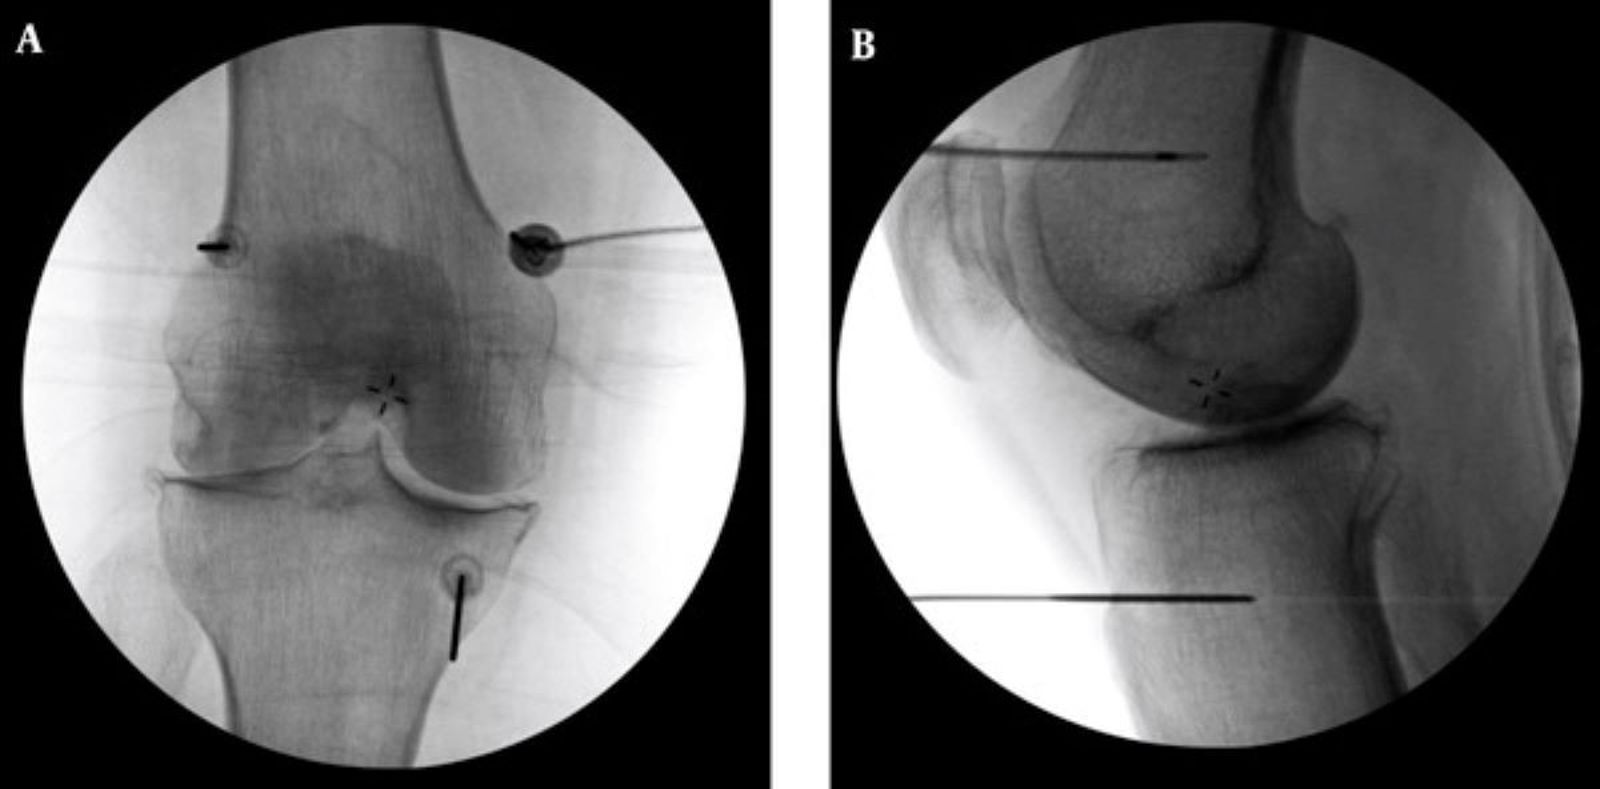

治療在局部麻醉下進行,透過X光定位將電極導針導引至膝蓋3個主要感覺神經叢,輸出高頻電波,使疼痛神經失去傳導能力。術前會測試不同電量並請患者活動膝蓋,確保不影響日後關節活動。效果通常在術後當下至一週內顯現,可維持半年至兩年。